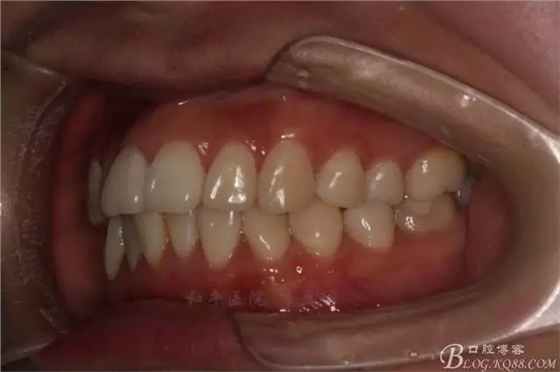

該病例主要為17、27頰側(cè)位同時(shí)伴有伸長(zhǎng),當(dāng)然種植支抗可以解決,但還有簡(jiǎn)單實(shí)用的辦法嗎?如圖,在橫腭桿遠(yuǎn)中延伸出牽引鉤,位置盡量遠(yuǎn)離合平面,7粘舌側(cè)扣,牽引力的方向?yàn)閴旱图吧嘞?,下圖為兩個(gè)月的效果,17已到位,27還未到位。